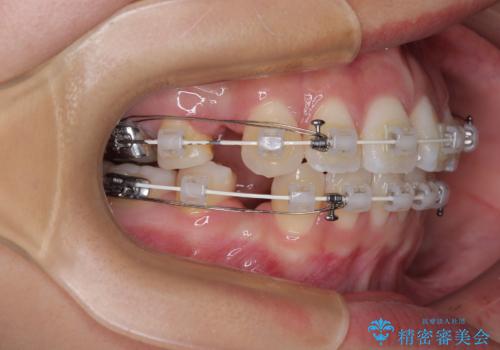

- 矯正装置

- 審美装置

- 前歯が突出して、眠るときに口が開いてしまうことを気にして来院された患者様です。

横から見た際の口元の飛び出した印象も改善したいとのことで、上下左右の第一小臼歯4本を抜歯し、ワイヤー装置にて抜歯矯正を行うこととしました。

舌の突出癖改善のためのトレーニングをしっかりと実践してくださり、2年強の治療期間でしっかりと仕上げることができました。